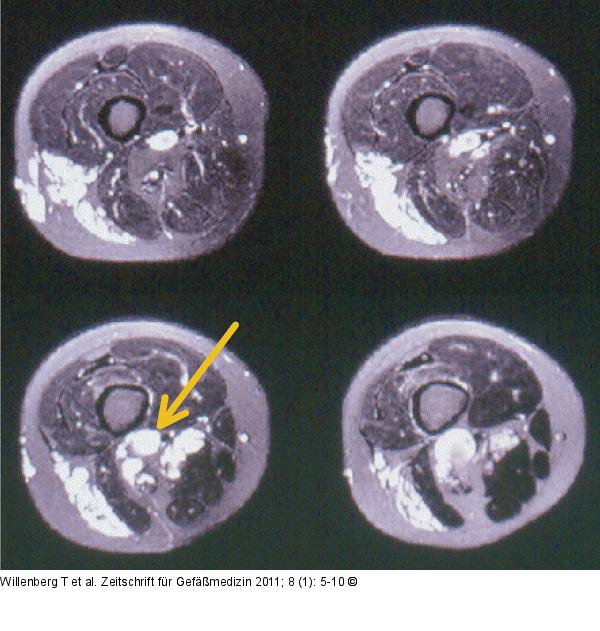

Abbildung 2: MR-Angiographie T2-gewichtete Aufnahmen der MR-Angiographie zeigen die extratrunkalen und trunkalen (Aneurysma der Vena poplitea, Pfeil) der venösen Malformation. |

T2-gewichtete Aufnahmen der MR-Angiographie zeigen die extratrunkalen und trunkalen (Aneurysma der Vena poplitea, Pfeil) der venösen Malformation. |